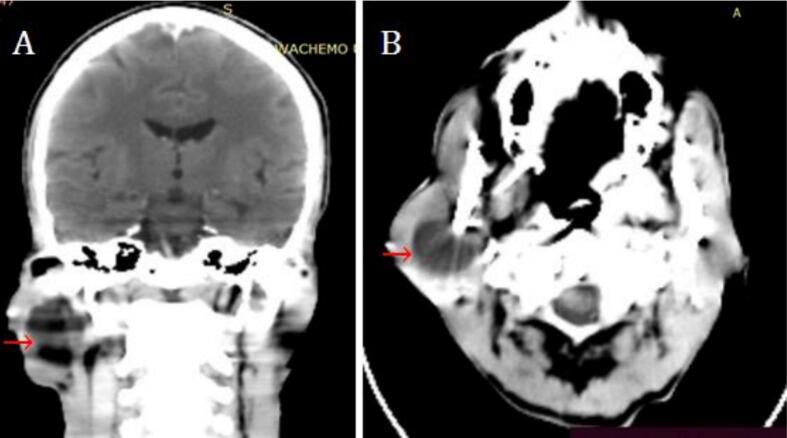

对患者进行了头部CT扫描和细针穿刺细胞学检查(FNAC)。CT扫描显示,右侧腮腺病变边界清晰,液体衰减,大小为2.7×2.8×3.2cm,边缘光滑。未观察到增强(图2)。在细针穿刺细胞学检查中,吸出12毫升稻草色液体。抽吸后肿胀消退,并立即重新填充。细胞学检查显示,在流体背景中有几簇基底细胞。鉴于这些发现,诊断为良性囊性肿瘤。

图2 CT扫描显示右侧腮腺囊性病变(红色箭头)